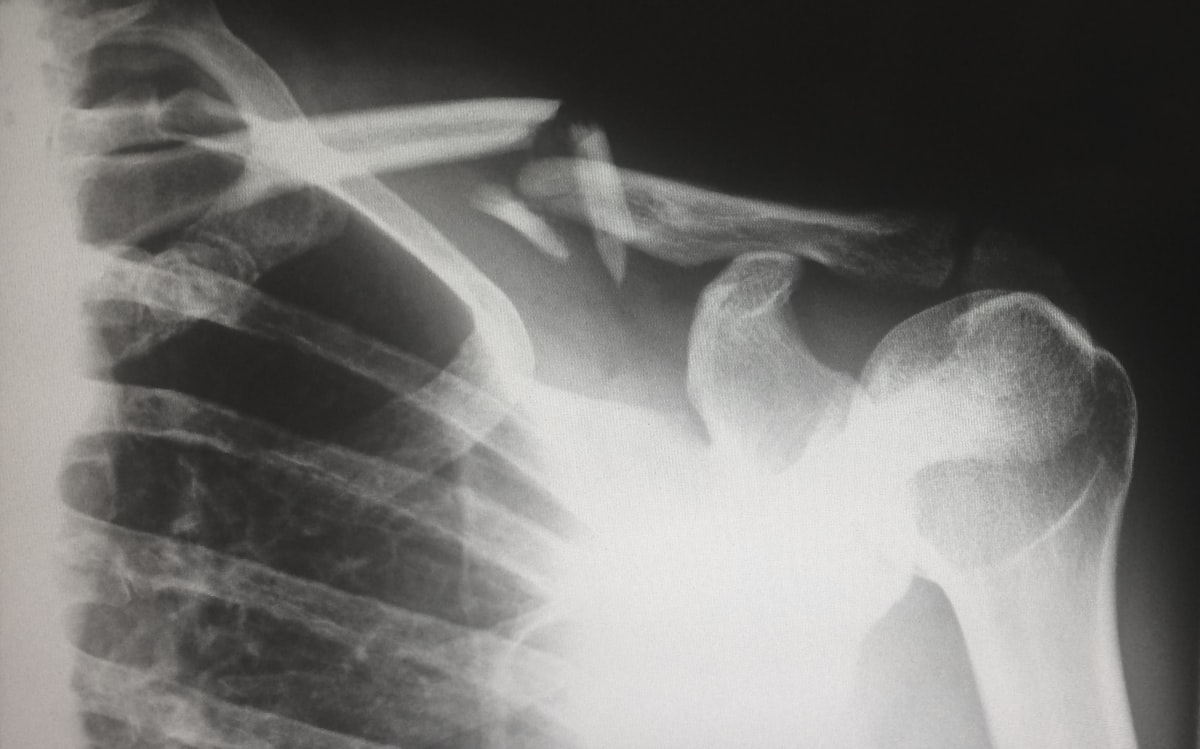

Рентгенологический кабинет Махачкалинской клинической больницы оснащён современным цифровым рентгеновским оборудованием, обеспечивающим высокое качество снимков при минимальной лучевой нагрузке на пациента.

• Опорно-двигательный аппарат и челюстно-лицевая область:

Рентгенография костей, суставов и позвоночника (в различных проекциях), рентгенография черепа, придаточных пазух носа и зубов. Выполняются специальные укладки черепа (по Шюллеру, по Майеру).